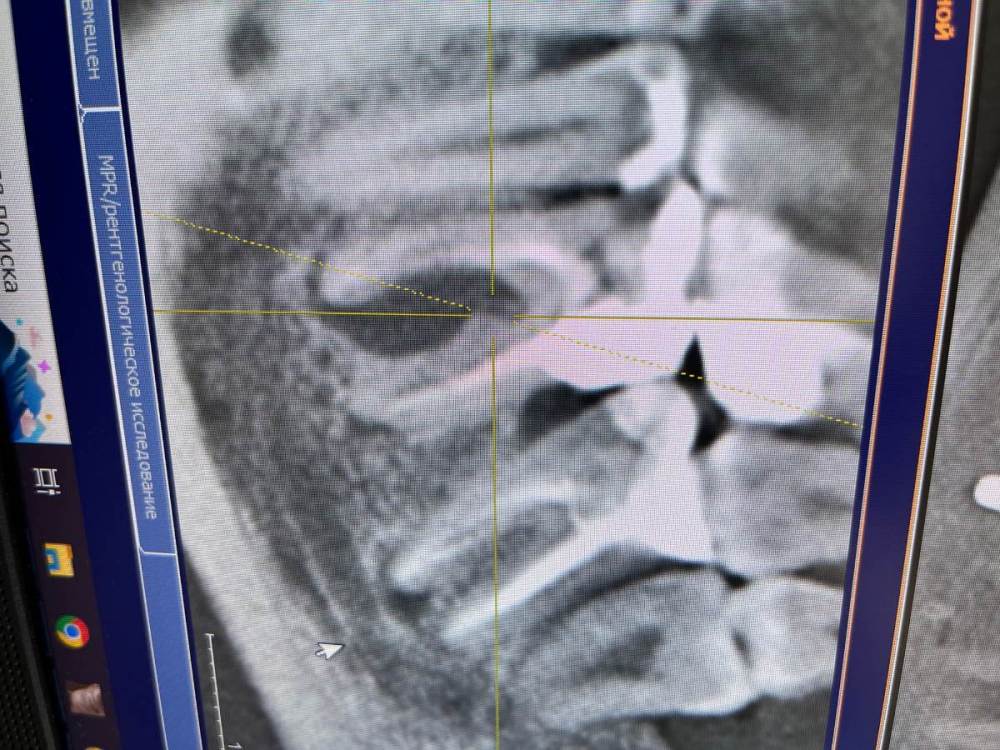

Спустя месяц после установки коронок у меня воспаляется киста на 36/37 зубе , так как давление на нее увеличилось и мне предлагают его удалить и поставить имплант.

Высылаю фото отпечатков при прикусе , мою искривленную улыбку  панараму 2016 года до имплантации и сейчас. Так же ситуацию с 36.37

220825095808-Гумеров Н.Р.-общие-Хорошилова Т.Н.eb87a02b7aed4eb3b20dfaea7b4aef0f.jpg